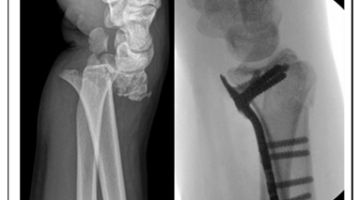

Quizvraag: Wat hebben avontuurlijke jongens met oudere dames gemeen? Het antwoord: polsbreuken. De ene groep omwille van gewaagder gedrag, de andere door poreuze botstructuren. Maar sowieso zijn polsbreuken de meest voorkomende van alle breuken. En uit studies blijkt dat bij complexere gevallen 1 op 4 patiënten binnen het jaar terugkeert voor een tweede ingreep. Specifix, een spin-off van Universiteit Antwerpen, wil dat patroon doorbreken met een AI-gestuurde preoperatieve workflow. Die moet vóór de operatie al duidelijk maken welke plaat en schroeven het best passen bij de patiënt en de breuk. Ondersteund met een VLAIO ontwikkelingsproject en een haalbaarheidsstudie moet hun technologie de polschirurgie wereldwijd verbeteren en versnellen.

Alejandra Ortega, CEO van Specifix: “In de huidige, ‘klassieke’ polschirurgie gebeurt veel finetuning tijdens de operatie zelf: de chirurg analyseert, selecteert, positioneert de fixatieplaat, controleert onder doorlichting, corrigeert en controleert opnieuw vanuit zijn expertise- en ervaring. Het is erg tijdrovend en gaat met heel wat extra (re)sterilisatie gepaard, wanneer een gekozen plaat toch niet de meest geschikte blijkt. SPECIFIX verschuift dat soort van ad hoc beslissingen naar de preoperatieve planning. Onze AI-tool analyseert de breuk en maakt een onderbouwde voorselectie van het implantaat en de juiste schroeven. Als de chirurg dat wenst kunnen we meteen ook een geprinte boorgeleidingsmal bezorgen.”

Alejandra: “Onze oplossing maakt het leven van de chirurg makkelijker door het meest geschikte implantaat voor de meest optimale fixatie te suggereren, gebaseerd op de patiëntspecifieke anatomie en het fractuurpatroon. Dat biedt voor alle betrokkenen alleen maar voordelen. Voor patiënten betekent het een snellere en minder pijnlijke revalidatie. Voor chirurgen betekent het efficiëntere en tegelijkertijd kortere operaties. Onze pilots tonen aan dat een vlottere voorbereiding kan resulteren in 10 tot 20 minuten tijdswinst per ingreep. Ziekenhuizen vinden het interessant als operaties minder tijd in beslag nemen en minder operatief afval opleveren. En laten we de betere reputaties van artsen en ziekenhuizen ook maar vermelden, want tevreden patiënten delen graag hun positieve ervaringen.”

Ondersteund door een VLAIO ontwikkelingsproject bouwt Specifix de end-to-end workflow in verschillende stappen uit: de automatische segmentatie van de botfragmenten, het herpositioneren van de botfragmenten naar de correcte anatomische positie, en vertaling naar de best passende vorm en positie van de plaat en schroeven die in de operatiezaal reproduceerbaar is (optioneel via een 3D-geprinte gids). Alejandra: “De AI-rekentijd bedraagt enkele minuten en resulteert in meetbare tijd- en kwaliteitswinst in het operatiekwartier.” Parallel loopt er ook een VLAIO haalbaarheidsstudie die de Specifix AI-tool betrouwbaarder én makkelijker inzetbaar moet maken. “We willen de klinische intuïtie van de ervaren chirurg in ons systeem integreren met een ‘sanity check’”, legt Alejandra uit.